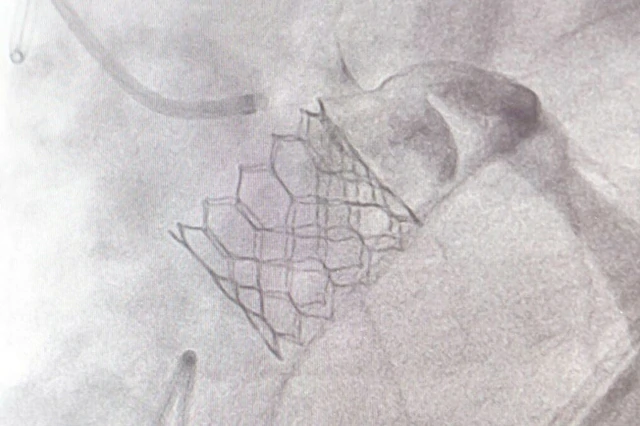

ศูนย์หัวใจสิริกิติ์ ภาคตะวันออกเฉียงเหนือ มหาวิทยาลัยขอนแก่น ยกระดับการรักษาผู้ป่วยโรคลิ้นหัวใจเอออร์ติกตีบรุนแรง ด้วยหัตถการ TAVI (Transcatheter Aortic Valve Implantation) หรือการเปลี่ยนลิ้นหัวใจเอออร์ติกโดยไม่ต้องผ่าตัดเปิดหน้าอก ซึ่งเป็นเทคโนโลยีที่ช่วยลดความเสี่ยงและเพิ่มความปลอดภัย โดยเฉพาะในผู้ป่วยสูงอายุหรือผู้ที่ไม่เหมาะสมต่อการผ่าตัดใหญ่

รศ.นพ.ดนณ แก้วเกษ อายุรแพทย์หัวใจและหลอดเลือด ศูนย์หัวใจสิริกิติ์ ภาคตะวันออกเฉียงเหนือ กล่าวว่า โรคลิ้นหัวใจเอออร์ติกตีบขั้นรุนแรงเป็นภาวะที่พบได้มากในผู้สูงอายุ และอาจนำไปสู่อาการเหนื่อยง่าย เจ็บหน้าอก เวียนศีรษะ หรือภาวะหัวใจล้มเหลวได้ การรักษาแบบดั้งเดิมคือการผ่าตัดเปิดหน้าอกเพื่อเปลี่ยนลิ้นหัวใจ แต่ผู้ป่วยบางรายมีความเสี่ยงสูง ไม่เหมาะกับการผ่าตัด วิธี TAVI จึงเข้ามามีบทบาทสำคัญ ซึ่งข้อดีของ TAVI คือไม่ต้องเปิดหน้าอก ไม่ต้องหยุดหัวใจ โดยแพทย์จะผ่าตัดใส่ลิ้นหัวใจเทียมผ่านทางหลอดเลือดแดงที่ขาหนีบ ทำให้ผู้ป่วยฟื้นตัวเร็ว หลายรายสามารถกลับบ้านได้ภายใน 2–3 วัน

สำหรับขั้นตอนการรักษา ศูนย์หัวใจสิริกิติ์ฯ ได้ใช้เทคโนโลยีลิ้นหัวใจรุ่นใหม่ที่พัฒนาให้วางตำแหน่งได้แม่นยำ ลดความเสี่ยงของภาวะแทรกซ้อน เช่น เลือดออก หลอดเลือดบาดเจ็บ หรือการนำไปสู่ภาวะการเต้นผิดจังหวะ ทีมแพทย์ Heart Team ซึ่งประกอบด้วยแพทย์โรคหัวใจ แพทย์หัตถการ แพทย์ศัลยกรรมหัวใจ วิสัญญีแพทย์ และทีมพยาบาลเฉพาะทาง จะร่วมกันวางแผนการรักษาและประเมินอย่างละเอียดในผู้ป่วยแต่ละราย เพื่อให้ได้ผลลัพธ์ที่ปลอดภัยที่สุด